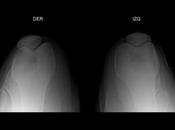

Hipertensión pulmonar persistente del RN

. Cianosis intensa + taquipnea. Shunt D-I. Dx. Prueba de hiperoxia, pO2 menor a 50, cardiopatía (Tx prostaglandinas). Menor de 10 HPPRN, mas de 250, problema... Leer el resto